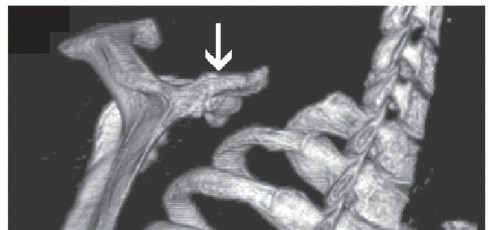

Computed Tomography (CT) with 3D volumetric reconstruction is the gold standard for evaluating the osseous morphology of the superomedial angle. It precisely delineates the anterior curvature of the scapula, identifies osteochondromas, and assesses thoracic cage congruency.

The osseous anatomy of the scapula exhibits significant inter-individual variability. The mean superomedial angle of the scapula is estimated to range between 139 and 154 degrees, with the average thickness of the superior pole measuring 3.4 to 3.9 mm. A prominent superomedial angle, sometimes referred to as Luschka’s tubercle, significantly increases the risk of mechanical impingement against the underlying ribs during scapular protraction and retraction.